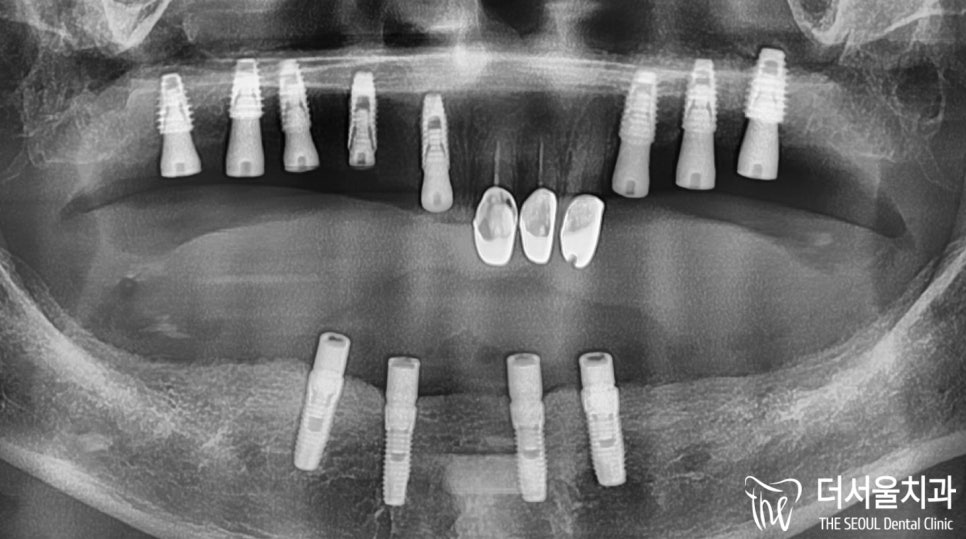

뼈이식과 픽스처, 힐링 어버트먼트 세팅까지

모두 완료했습니다.

워낙 골폭이 없었던 터라

약 5개월이라는 기간이 소요되었습니다.

안정감있게 고정이 잘 되었네요.

이제 최종 보철 제작에 들어갑니다.

엑스레이로 한번 더 마지막 체크를 했습니다.

계획에 맞춰 좋은 결과를 얻었습니다.